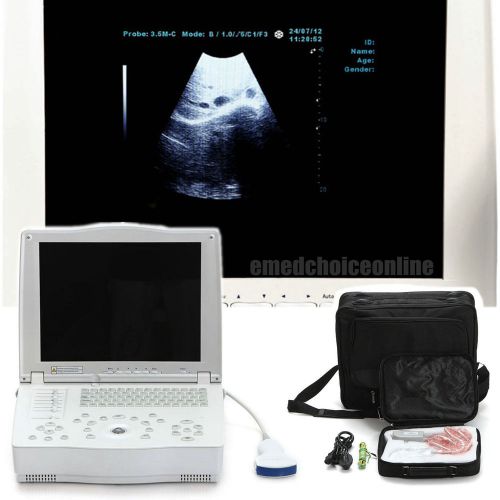

FDA Full Digital Laptop 15-inch Ultrasound Scanner +Convex Probe + Free 3D CE

FULL DIGITAL LAPTOP ULTRASOUND SCANNER MACHINE + CONVEX PROBE CE 100% WARRANTY